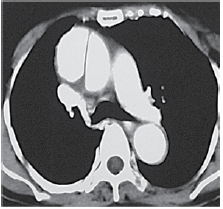

Homem de 37 anos é internado devido dor intensa em todo o braço esquerdo iniciada há 30 minutos. Encontra-se bastante ansioso e agitado pedindo ajuda. Pressão arterial (MSD): 230 x 170 mmHg. Uma tomografia com contraste foi realizada e ilustrada a seguir.

Enunciado 3309344-1

Em relação à dor no braço, é correto afirmar: